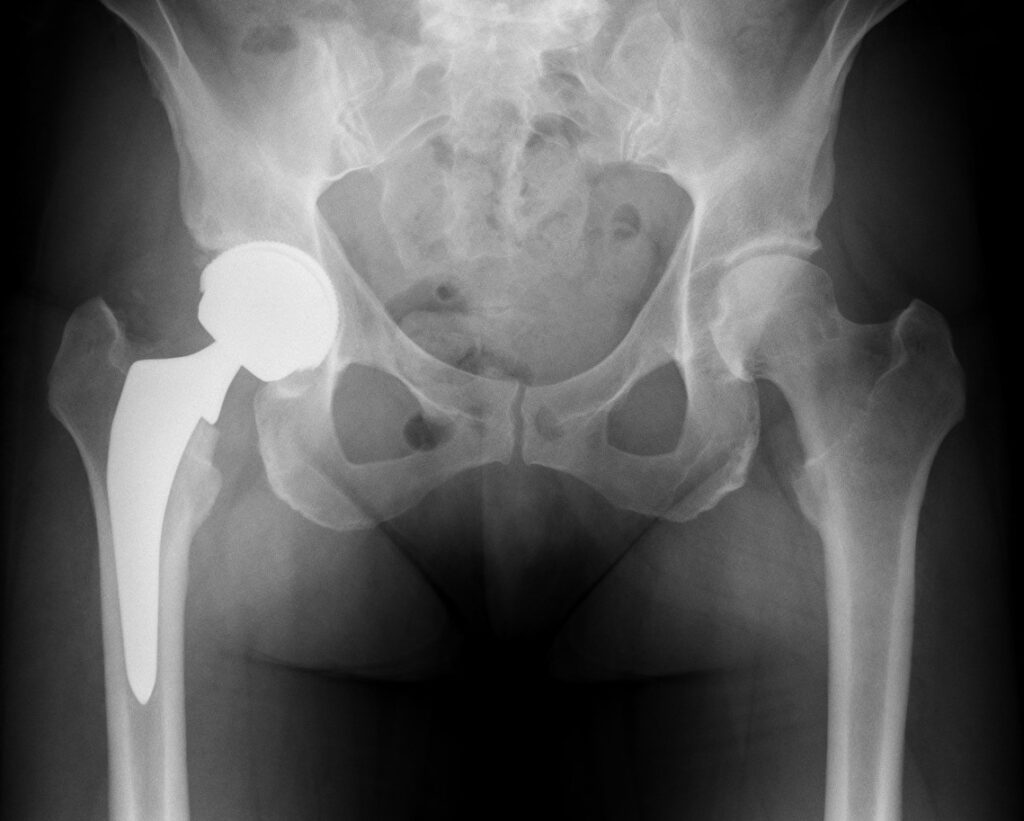

During the procedure, the worn-out surfaces of the hip are replaced with smooth, artificial components. These implants replicate the natural ball-and-socket function of the hip and are designed to provide long-lasting, stable movement with minimal friction or wear.

Example of Total Hip Replacement